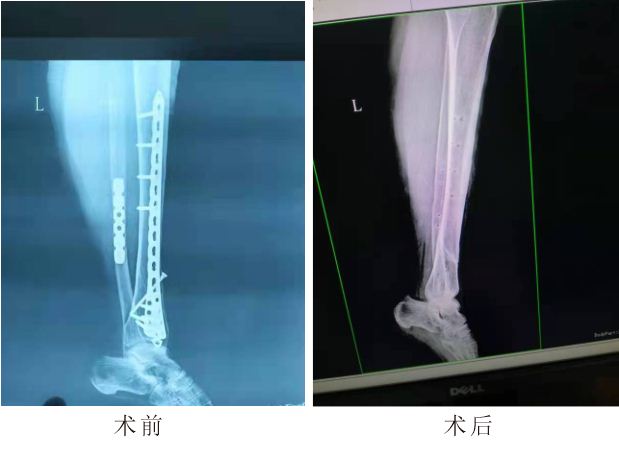

(术前术后片子)

该患者为资中县龙结镇农民,于2018年在成都工地打工时不慎受伤,致右胫腓骨粉碎性骨折,在成都某一三甲医院行手术治疗,病情好转出院,评估为9级伤残,此后患者在家休养,逐渐患者发现右小腿皮肤下方螺钉触手可及,有活动感,动辄痛甚,没有引起重视。最近,患者右小腿不适感加剧,遂前往资中县龙结镇卫生院就诊,以“右胫腓骨陈旧性骨折”收入住院,经过系列检查,资中县龙结卫生院院长赵万里积极与支援中医专家组长肖启树进行会诊、讨论、病例分析后诊断右胫腓骨陈旧性骨折(螺钉变形断裂)。考虑到右胫腓骨陈旧性骨折,术后3年,病史较长,患者重体力劳动者,不排除术后再次损伤可能,故造成内固定螺钉疲劳,断裂可能性极大,经过术前的充分准备,内江市中医医院第15小组团队团结协作,肖启树副主任医师主刀,陈安丽护士长负责器械,心内科张云洪医师负责心电监护,动态掌握监测患者生命体征,保障生命安全。整个手术过程非常顺利,术后患者功能恢复良好。